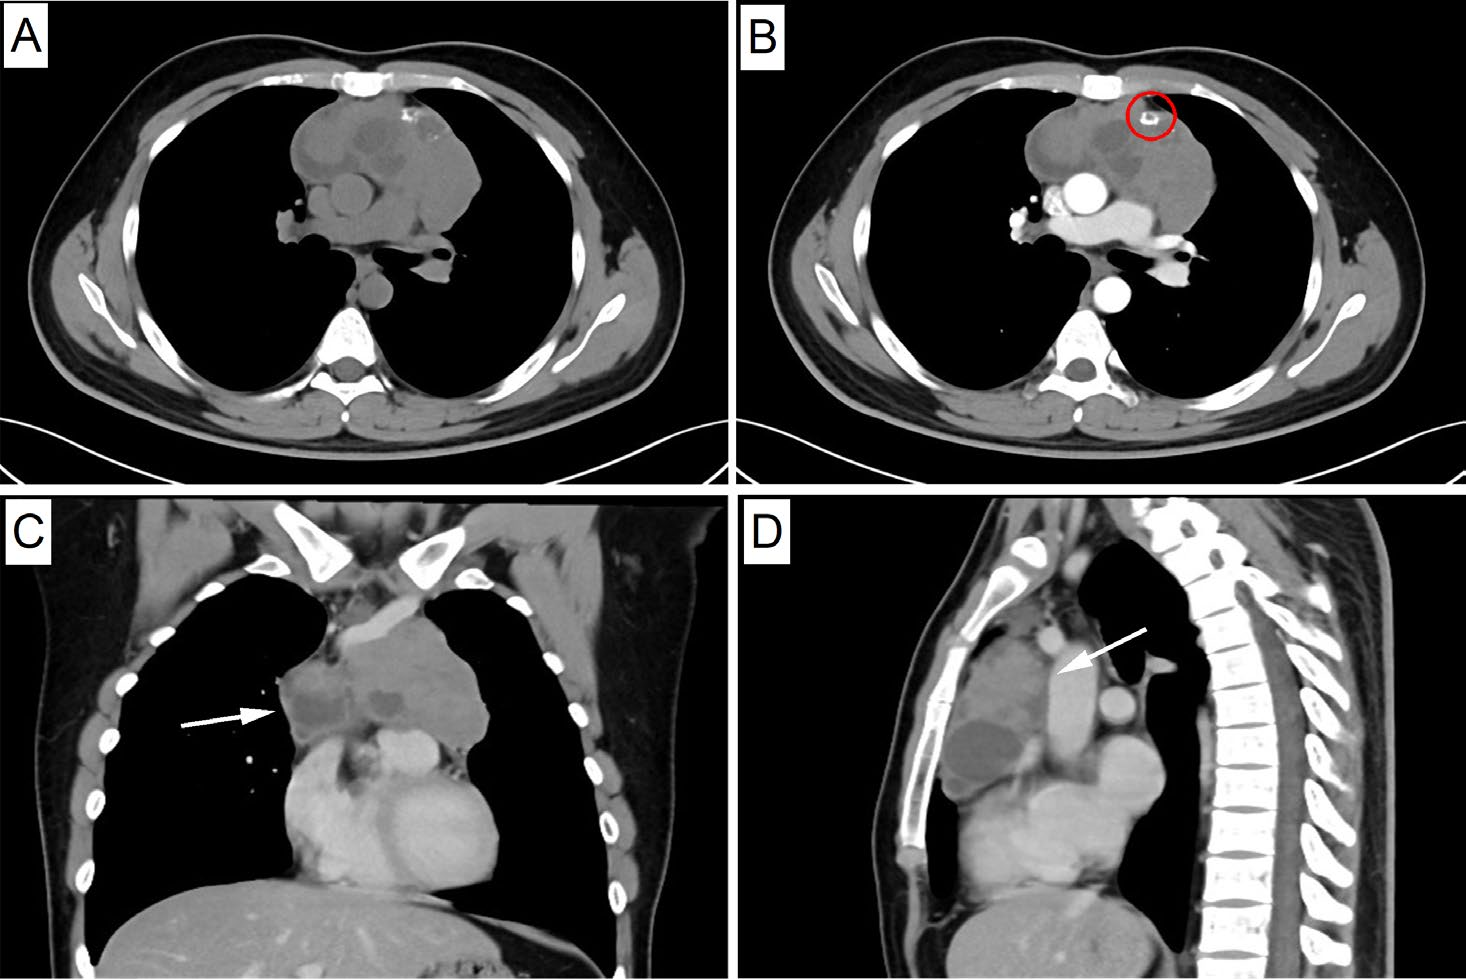

CT影像显示:前纵隔巨大囊实性肿块,大小约104×56×64mm,边界不清,伴有钙化及囊变,邻近心脏及大血管受压移位(图1A–D)。

图1. 术前CT影像示前纵隔囊实性肿块,边界不清,侵犯周围器官